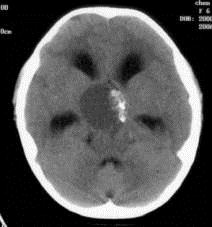

问题 病历摘要:??患者女性,6岁,半年来感觉视力模糊,近10天出现反复头痛,间有恶心呕吐,精神转差,查体:神志清楚,身高90cm,体重25Kg,血压90/55mmHg,右眼视力4.6,左眼视力4.8,双侧视乳头水肿,颈软,伸舌居中,四肢肌张力正常,肌力5级,双侧Babinski征(-)。 患者具有下列那些表现,可以诊断抗利尿激素分泌不当综合征?